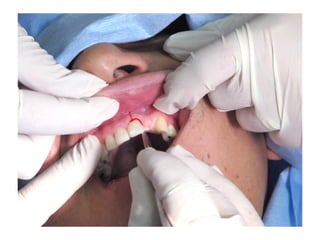

Area de defecto. Con prótesis a

utilizar durante el proceso de

integración del trasplante de hueso